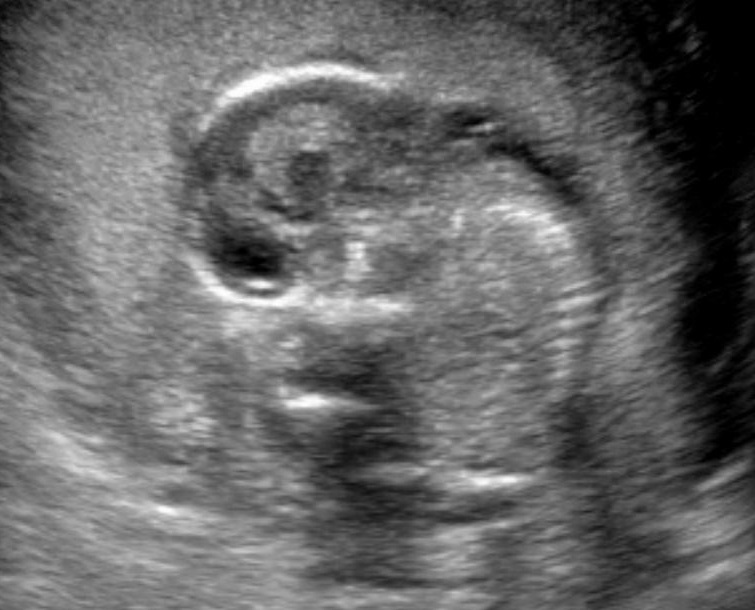

It has been shown that the subjective estimate of the amniotic fluid volume could be as accurate as the semi-quantitative measurements (Magann et al., 1997). This technique is adequate for use during early gestation.